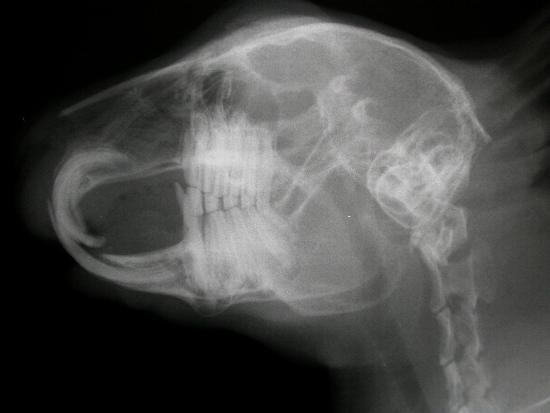

У них 28 зубів. Вони розташовуються і виростають в певній послідовності. На зображеннях нижче можна побачити будову щелепи кроликів.

Будова щелепи у кроликів

Варто зазначити, що для підтвердження діагнозу необхідно зробити рентген. На зображенні нижче наведено приклад нормального стану коренів зубів кролика.

Здорове стан щелепи